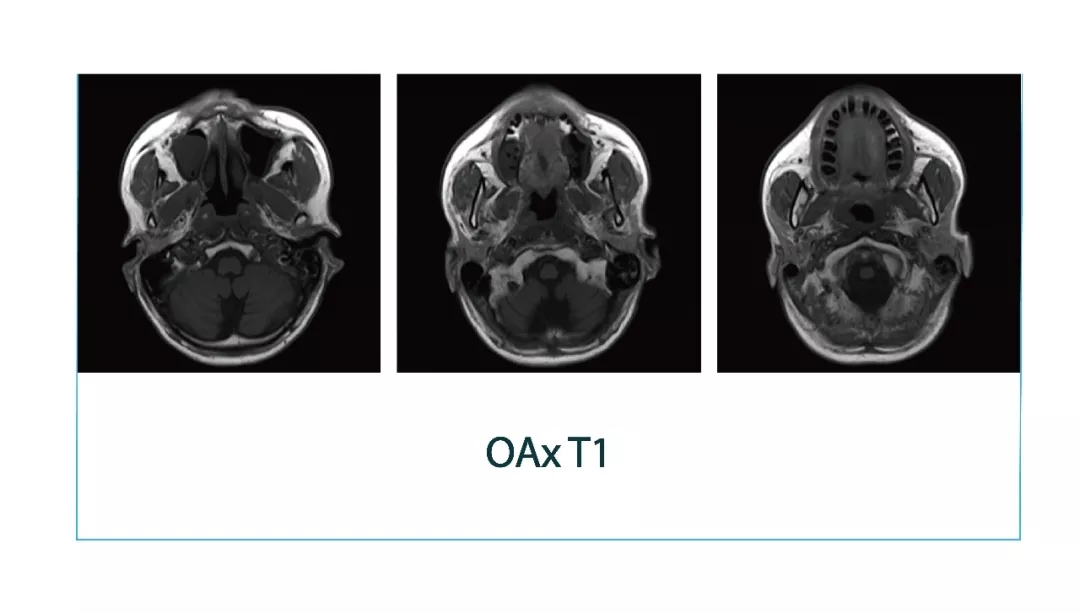

【朗润影像档案】磁共振影像病例分享(编号20180323)